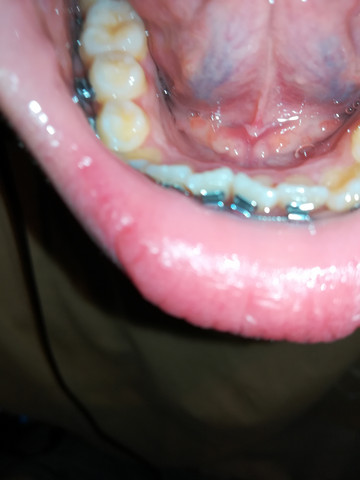

Fieberblasen oder Fieberbläschen können dazu führen dass schmerzhafte weiße Beulen unter Ihrer Zunge auf Ihren Lippen und auf der Innenseite Ihrer Wangen auftreten. Ein wichtiges Stomatitis-Virus ist das Herpes simplex Virus HSV 1 welches bei Kindern die Mundfäule Stomatitis aphtosa hervorruft. Herpes ist hochansteckend Aphthen dagegen nicht.

Beispiel für eine virale Ursache ist die sogenannte Herpes-simplex-Infektion. Sind Aphten wie Herpes. Die herpesartigen Blasen verbreiten sich vor allem auf der Innenseite der Lippe wachsen dort in großer Anzahl und schmerzen erheblich.

Im Rahmen der Infektion kann sich eine Mundfäule eine sogenannte Gingivostomatitis herpetica entwickeln. Wenn ich drauf drücke dann werden die länger.

Komischer Pickel Wunde Unter Der Zunge Arzt Entzundung Mund